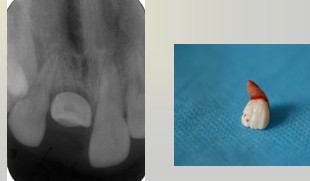

解析: 额外牙

额外牙对牙列的影响:恒牙的发育和萌出、牙间隙、牙齿移位、邻牙扭转、邻牙牙根吸收与正常牙融合、恒牙迟萌或阻生 — 含牙囊肿和美观。I其治疗包括:早期发现,适时拔除,及时拔除萌出的多生牙;择期拔除阻生的多生牙,以不影响正常牙发育为原则;埋伏无病变的多生牙,需要定期观察;可替代正常牙的多生牙应予保留。